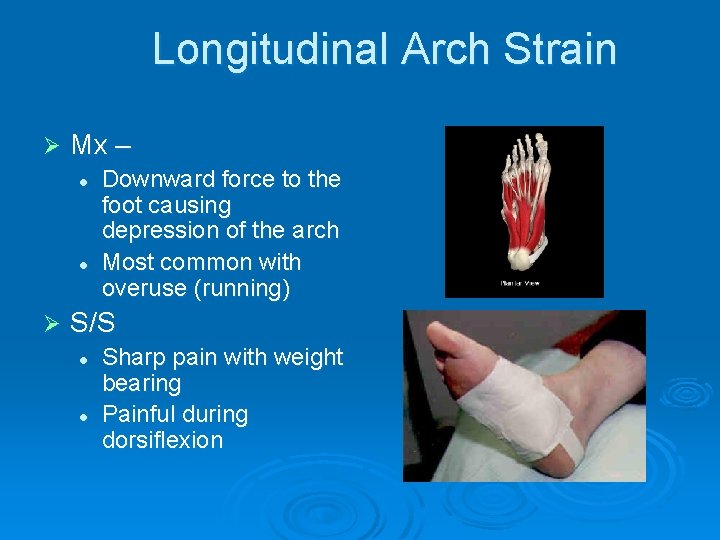

Longitudinal Arch Strain Ø Mx – l l Ø Downward force to the foot causing depression of the arch Most common with overuse (running) S/S l l Sharp pain with weight bearing Painful during dorsiflexion